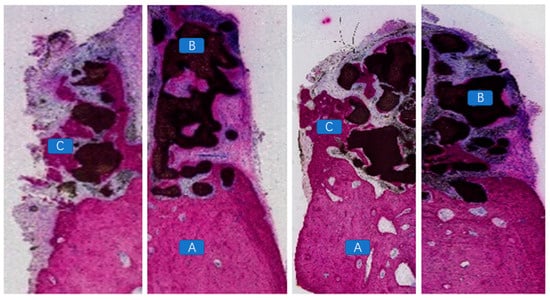

4.4. Histopathological Morphological Evaluation